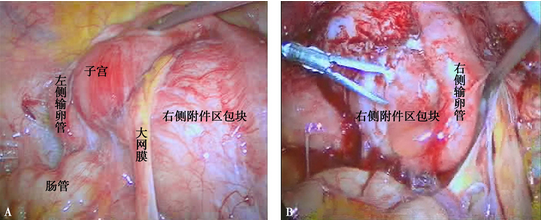

(1)炎症经子宫内膜向上蔓延 首先引起输卵管黏膜炎,输卵管黏膜肿胀、间质水肿及充血、大量中性粒细胞浸润,严重者输卵管上皮发生退行性变或成片脱落,引起输卵管黏膜粘连,导致输卵管管腔及伞端闭锁,若有脓液积聚于管腔内则形成输卵管积脓。淋病奈瑟菌及大肠埃希菌、类杆菌以及普雷沃菌,除直接引起输卵管上皮损伤外,其细胞壁脂多糖等内毒素引起输卵管纤毛大量脱落,导致输卵管运输功能减退、丧失。因衣原体的热休克蛋白与输卵管热休克蛋白有相似性,感染后引起的交叉免疫反应可损伤输卵管,导致严重输卵管黏膜结构及功能破坏,并引起盆腔广泛粘连。

衣原体感染导致盆腔广泛粘连

A.肠管、大网膜与子宫后方、右附件广泛粘连形成包块;B.右附件区包块来自右侧卵巢和输卵管,与周围组织粘连。